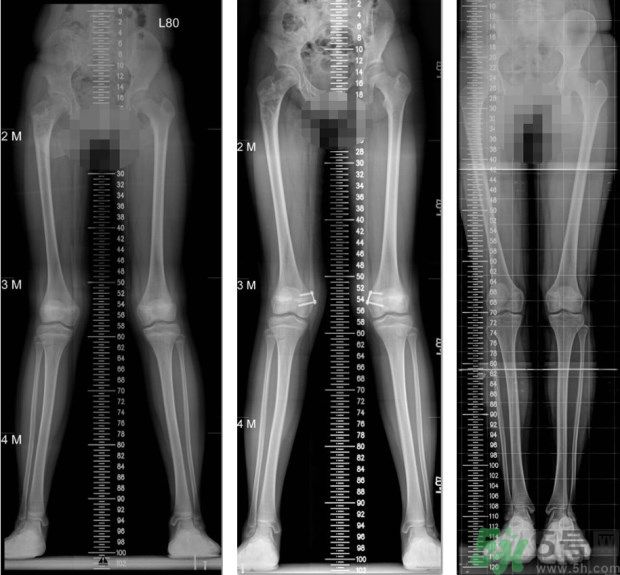

左圖:矯正前,11歲女童,大腿內(nèi)側(cè)的生長板過度發(fā)育,導(dǎo)致雙腳X型腿;中圖:矯正中,在大腿內(nèi)側(cè)的生長板,夾上小夾子,矯正過度發(fā)育的生長板;右圖:矯正後,經(jīng)過8個月的生長板導(dǎo)引,恢復(fù)筆直的雙腳。(照片提供:王廷明 醫(yī)師)